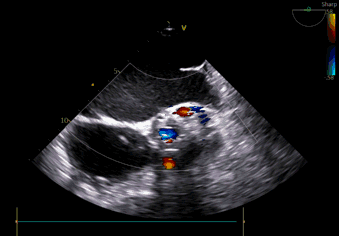

左冠灌注

瓣周漏

术中导丝跨瓣后20mm球囊预扩,超声判断冠脉风险尚可,植入L23 VenusA Plus可回收瓣膜位置良好,用23mm球囊后扩支架下缘,微少量瓣周漏。

术后即刻血压135/65mmHg,狭窄解除,释放后超声测量瓣下支架长度6mm标准位释放瓣膜位置完美。整台手术用时不足1.5小时,麻醉、超声等团队全程协作为手术顺利完成保驾护航。